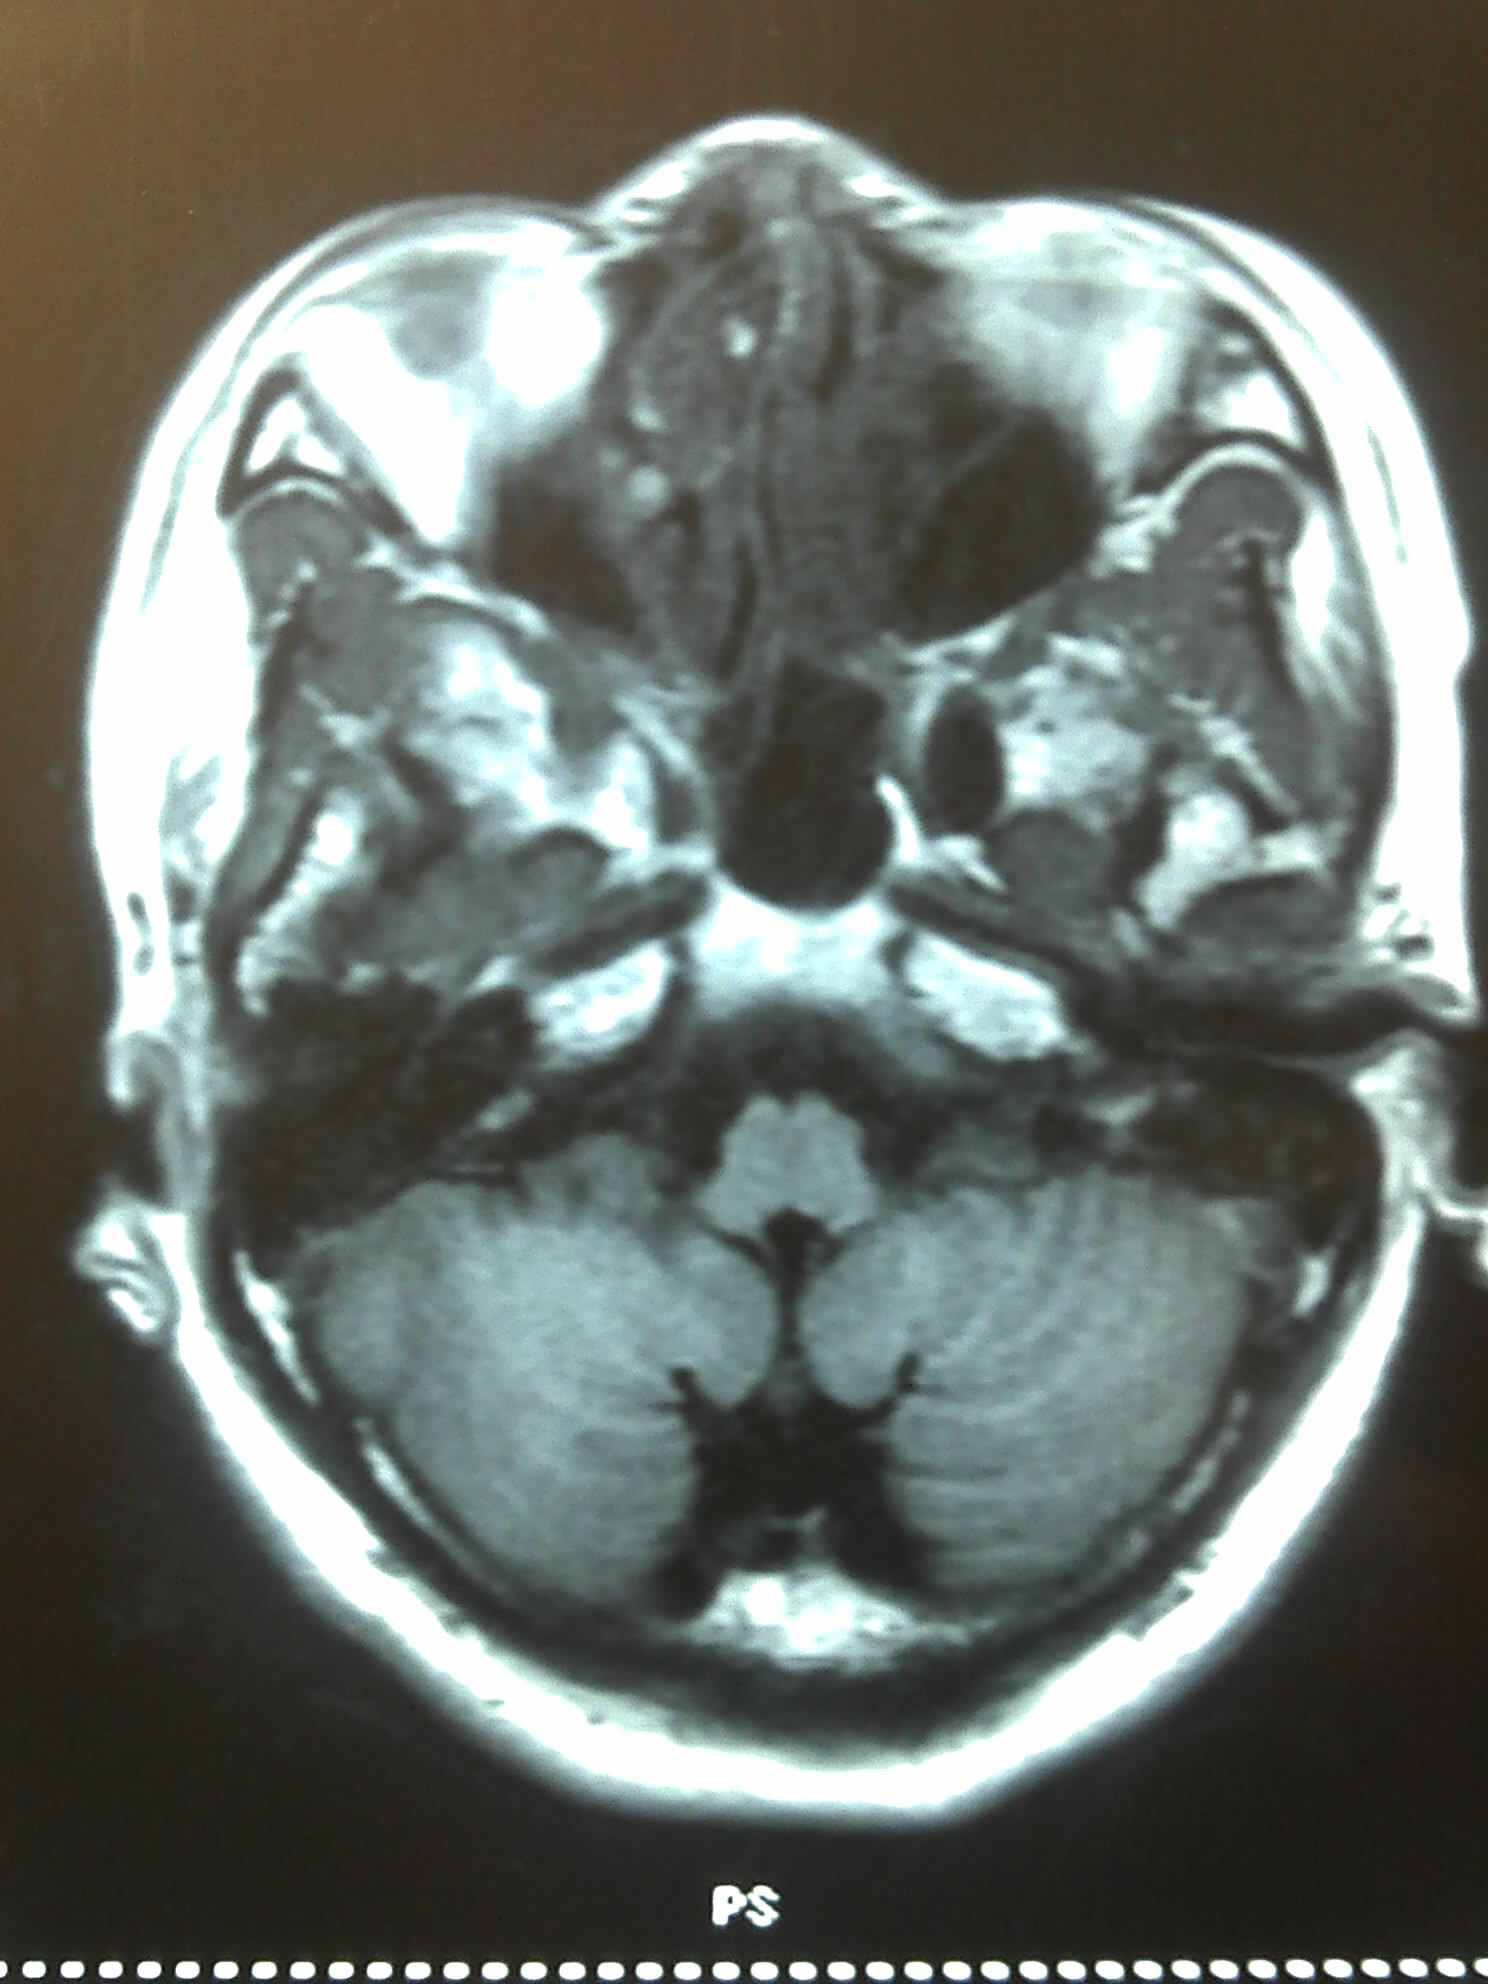

下图是患者的影像表现: